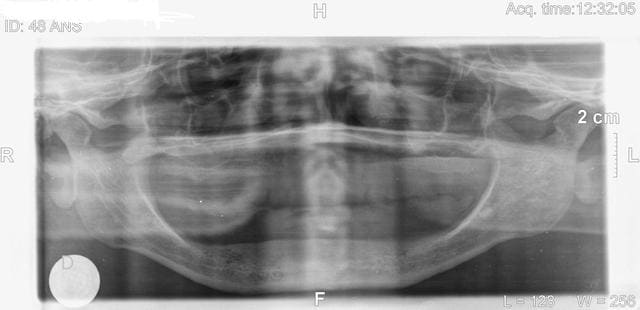

étant debutant je vous demande de me conseiller pour ce cas:femme 48 ans en bonne santé,désire implants mandibulaire pour stabiliser sa pothèse,mais j'hésite car crête fine ,

qu'en pensez-vous.

c'est quoi cette téléradiographie de profil bizarroïde? j'ai jamais vu ça, c'est ininterprétable, c'est à refaire.

ton bilan radio est faussé dès le départ, sinon fait un scanner de la mandibule.

La téléradio doit impérativement être à 5 m pour être à l'echelle 1 (enfin je crois), on dirait que celle ci a été shootée à 100m!

pourrais tu nous en dire en peu plus sur l'anamnèse de cette patiente. A la vue de la téléradio de profil la crête est sacrément résorbée pour une femme de 48 ans!

Ton cas est loin très simple pour commencer en implanto :

- résorption importante de la crête ce qui induit plusieurs difficultés : d'une part la proximité du plancher avec toutes les complications que cela peut engendrer, d'autre part un placement implantaire délicat si tu ne tiens pas compte de la résorption centrifuge de la mandibule par rapport au maxillaire.